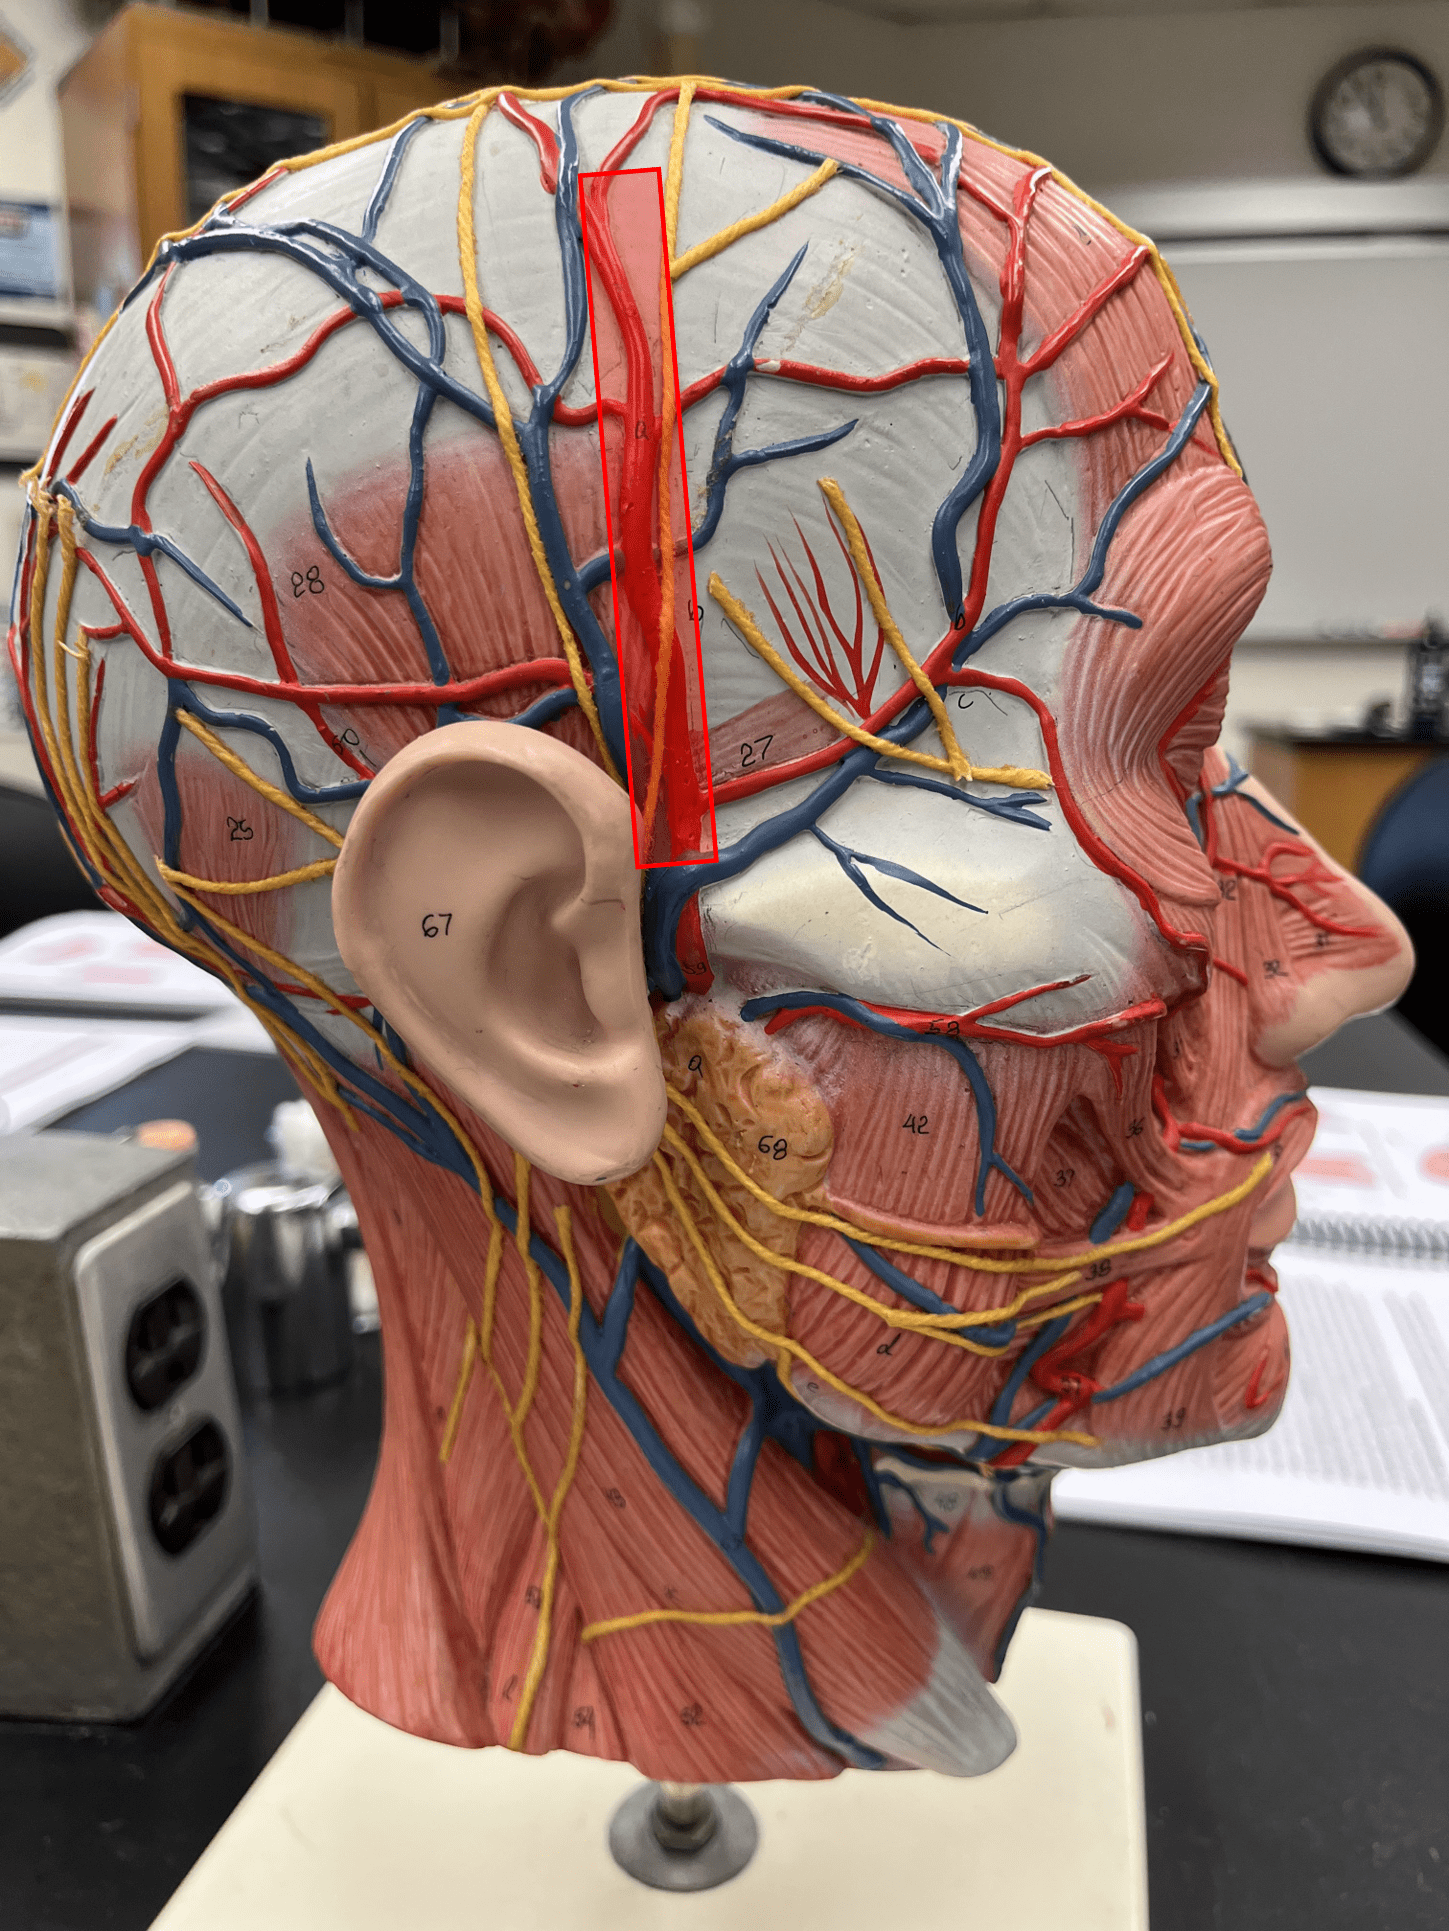

superficial temporal artery

• An artery of the head and neck.

• Originates from the external carotid artery.

• Supplies the chewing muscles, nasal cavity, lateral face and scalp, and dura mater.

• Originates from the external carotid artery.

• Supplies the chewing muscles, nasal cavity, lateral face and scalp, and dura mater.